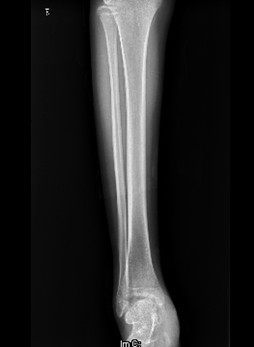

患者男,15岁,因“车祸致右足跟部皮肤撕脱伤清创缝合术后13天”入院。患者13天前因车祸导致右足疼痛流血伴功能障碍,右足跟部皮肤撕脱,遂到当地人民医院就诊,诊断为右跟骨骨折伴跟部皮肤严重剥脱伤,右胫骨远端骨折。急诊下行“右足跟部皮肤严重剥脱伤皮肤严重挫裂伤清创缝合术”。术后给予止痛、消肿、预防感染等对症处理,目前右足外侧及跟部皮肤变暗,坏死。患者为进一步诊疗,故转入我科继续治疗。

查体:右足内踝、外踝及跟部皮肤变暗,部分缺血坏死。未见畸形,稍肿胀。右足趾皮温无明显降低,右足趾感觉未见明显异常。右足内踝、外踝及跟部皮肤局部压痛。右踝关节活动受限,右踝关节活动诱发疼痛。右膝关节活动未见明显异常。 辅查:x片示右跟骨,右胫骨远端骨折。

诊断:1、右足清创缝合术后皮肤软组织坏死伴感染,2、右跟骨骨折,3、右胫骨远端骨折。 治疗:择期手术。